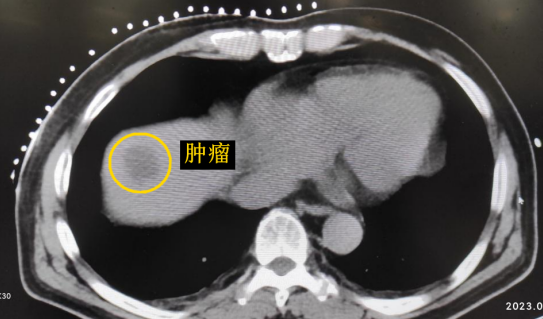

患者老年男性,曾于2021年行結腸癌手術。幾月前,發現肝臟轉移瘤,但沒有干預。近期CT顯示該轉移瘤明顯增大,并發現另一處轉移灶。

影像診療科陳寶瑩主任團隊評估后指出,較大的腫瘤位于肝頂部緊貼膈肌,如果繼續發展,腫瘤很可能突破肝包膜侵犯到膈肌,建議及時干預。病變緊臨膈肌,如果要完全消融,膈肌損傷的可能性就比較大,與其他局部治療方式比較,冷凍消融對周圍臟器、血管及神經損傷的可能性較小、安全性更高、患者疼痛感較輕,建議通過CT精準引導下經皮微創冷凍消融治療。

CT精準定位腫瘤